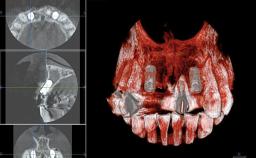

A 30-year-old woman was referred by her general dentist for evaluation of an esthetic complication related to previous implant treatment for congenitally missing maxillary lateral incisors. The patient’s chief complaint was the inadequate esthetic appearance of her smile. The case demonstrates the use of a combined approach to achieve optimal results. Two different flap designs - a tunnel technique and a coronally advanced flap - are employed based on the surgical objectives for the affected site.

# of Teeth 2

# of Implants 2

Type of Implants Two-Piece

Bone Augmentation No

Bone Volume Horizontally and vertically sufficient Horizontally deficient Deficient vertically or deficient vertically AND horizontally

Bone Volume Horizontally and vertically sufficient